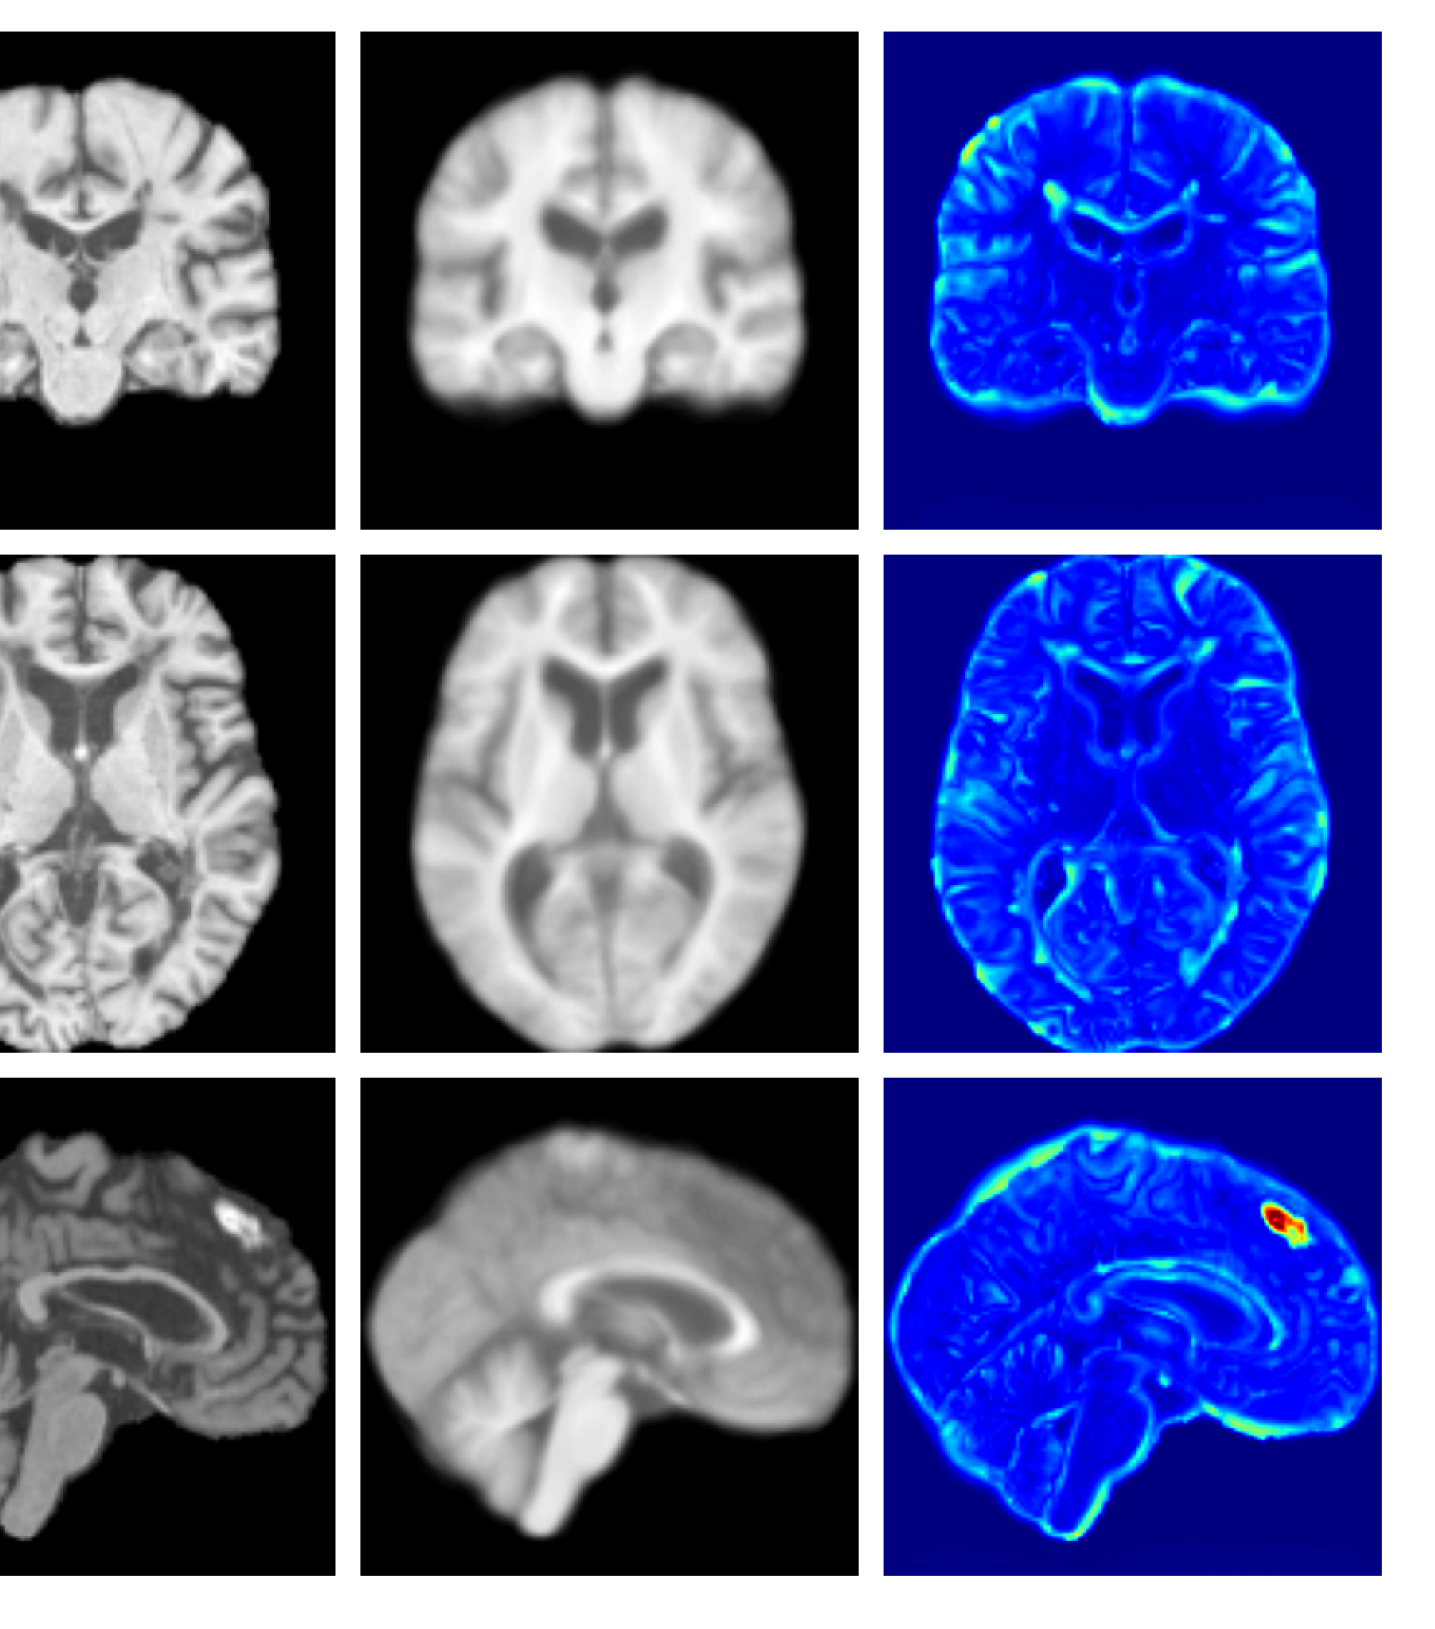

Figures 3 and 4, show example reconstructions and abnormality maps for a sample from the UKBB and UoTH datasets, respectively. Enlarged figures and additional example qualitative results for the ADNI dataset are available in the Supplementary. In Figure 3 we see that whilst all models are able to detect the lesion visible in the sagittal slice, the VAE, cVAE, LDM and LDM (TavgT_{avg}) produce very smooth outputs or lose defining characteristics and thus exhibit more false positives in healthy tissue. THOR and CADD provide the best results, with CADD better detecting white matter hypointensities (WMH). However, neither method fully inpaints all WMH, potentially due to presence of WMH in the healthy training set.

Figure 7 provides example reconstructions and anomaly maps for a healthy subject from the UK Biobank holdout test cohort.

Figure 7: Example healthy reconstructions and anomaly maps for a sample from the UK Biobank healthy test cohort. For a healthy subject, we should observe no regions highlighted in the anomaly map.